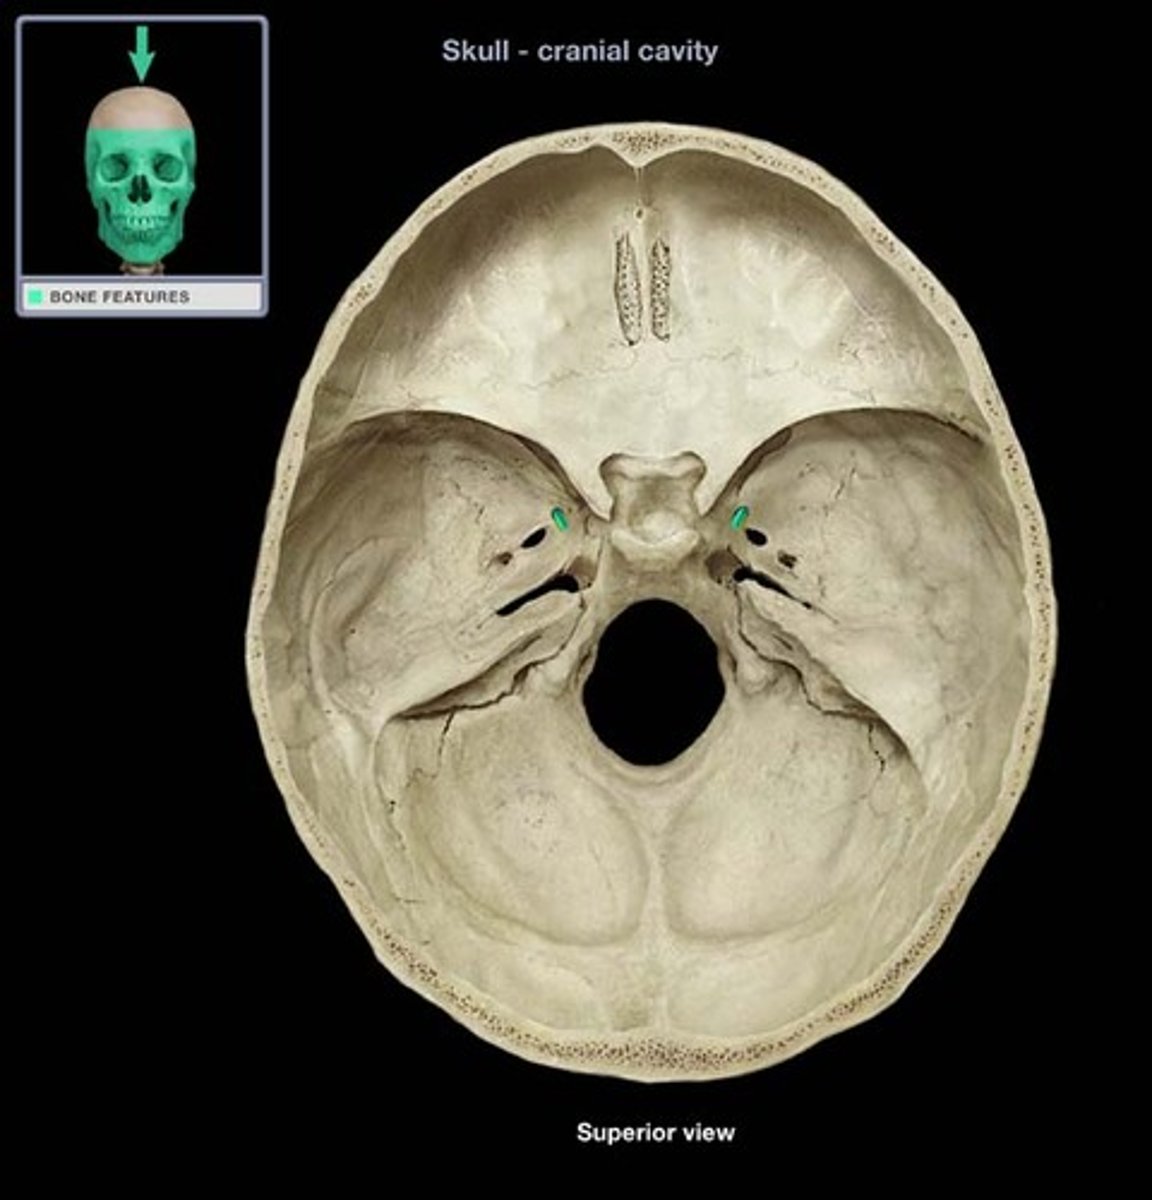

Petrous region

Includes the internal acoustic meatus/internal auditory canal